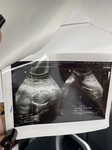

น้ำหนักน้องน้อยไปมั้ยคะ

ตอนนี้21w น้ำหนักน้อง140กรัมเองค่ะ ถ้าน้ำหนักน้อยต้องบำรุงอะไรบ้างคะน้ำหนักถึงจะขึ้น